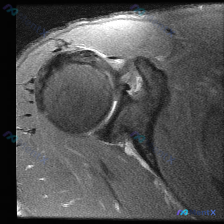

这个肩部MRI:冈上肌撕裂还是盂唇病变?

看到一份肩部MRI的病例资料,用户提到观察到"盂唇病变",但影像报告显示冈上肌腱全层撕裂伴滑囊积液,关节软骨与盂唇尚完整。大家觉得这个病例更倾向于什么诊断?是单纯的肩袖撕裂,还是合并盂唇病变?欢迎讨论。

整理了一份肩部影像病例资料,核心情况如下: 1. 影像资料:肩部MRI T1加权冠状位序列 2. 核心疑问:临床怀疑盂唇病变,该序列影像下能观察到什么? 3. 初步影像所见:当前序列显示肱骨头、肩峰、冈上肌腱等结构大致完整,上方盂唇形态及信号未见明显异常,未见明确肩袖撕裂、骨性撞击征象。 想和大家讨...

整理了一份肩部MRI病例讨论材料,医生的核心问题是排查盂唇病变,但看影像发现了一些矛盾点。先放MRI T2序列冠状位的分析: 1. 骨性结构:肱骨头、肩峰及锁骨远端轮廓尚可,未见骨折线或骨髓水肿 2. 肌腱与肩袖:冈上肌腱在肱骨大结节止点处形态异常,连续性中断,T2高信号 3. 关节与滑囊:肩峰下-...

最近整理了一份肩部MRI的病例讨论材料,患者主要问题是肩部疼痛,但问题明确指向"盂唇病变"范畴。先看T2冠状位图像的关键发现: 1. 冈上肌腱在肱骨大结节止点处有显著高信号,连续性可能中断 2. 肩峰下-三角肌下滑囊有明显的高信号积液 3. 关节盂唇区域信号存在改变 大家觉得这个病例更符合哪种诊断?...

整理了一个肩关节MRI-T2序列冠状位的病例讨论材料,医生提问关注盂唇病变,但影像最突出的是冈上肌腱全层撕裂。这份病例的核心疑问点和影像发现存在一定不匹配,大家第一眼怎么看?